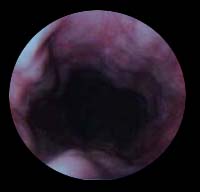

My need for a liver transplant became a reality in AUG 94 after finding that I had asymptomatic Hep-C combined with chronic alcoholic liver disease and had burst varices in my liver. I was sick and bled out and nearly dead but rebounded enough in two months to enter a recovery center and get on with trying to save my hide from the Hep Dragon and the Grim Reaper. At six months sober, I was evaluated by the UWMC transplant team. Evaluation and testing took 2 months and then I was placed on the type B liver transplant list as number two. Then the waiting began as I watched myself wasting away and getting sicker and more forgetful every day for the next 11 months. I was called at home and told to get right down to the hospital on 16FEB96 0900hrs. I was flustered and scared to death and didn't really want to go. When I got to the UWMC, University of Washington Medical Center, I was immediately so busy with preperation that I honestly did not have another chance to think about being scared. Drugs, showers, enemas, shaving, answering myrid questions, trying to memorize everyone's name. No pain, though. No painful procedures were done until I was knocked out at about 1500hrs. I woke up in the ICU the next morning. My wife and my mother were there waiting for me to regain consiousness. Yes, there was some pain but not anything unbearable. The only thing I found unbearable was the resperator and my incredable thirst. I tried to take the resperator out but my mother and the nurse stopped me. Later, I wrote a message to my mom and told her to go home and get some rest. While everyone had their back turned I pulled that damnable thing out. Then I demanded some ice chips or threatened to go get my own and I was in deadly earnest. What a relief those cool, wet chips gave me! I noticed the first sign of recovery the minute I awakened in ICU. The bursitis pain in my shoulders was completely gone! I don't know if it is the prednesone or my new liver functioning but it was a great relief! Also, I was completely helpless and dependant on everyone for the slightest thing. With no stomach muscles, I couldn't even shift in bed by myself. My kidneys shut down for a while and the inevitable swelling was difficult for a few days. I guess swelling of the privates is very common for men and women and damned uncomfortable, too. Sleeping on my back was never an option for me. I just can't do it! The minute I close my eyes, my soft palette falls back and I begin to choke. On top of that, the drugs were making me see the most terrible visions you could imagine. The second I closed my eyes all I could see was white tile floors, blood, slaughter, inhumanity, torture, sadism of every possible description done to all kinds of people. I truely thought I was going insane. These horrific images couldn't possibly come from a sane mind! I was given powerful drugs to try to relieve these images but nothing helped. I spent the first two weeks without sleep on my aching back. I was talking to people who weren't there, begging for some relief and some rest. Without the support of my wife and my mother I think I would have given up hope of recovery. My emotional state was pathetic. I was laughing and crying at the same time and had no control over anything. I couldn't watch TV or talk about anything upsetting. The first morning, I looked out the window with hazy eyes at a leafless tree dripping with cold Seattle rain. I immediately thought of a funeral under those gray, lifeless clouds with people mourning and grieveing and I just plain lost it for about two hours. I was sobbing non-stop and no consolation could make me feel any better. Fear becomes a tangible thing. There is just no way to explain this and I don't know if I will ever come to grips with it. It isn't fear of rejection or of change or of pain but instead a raw physical thing that makes my hair stand on end. I'm presently seeking professional psychiactric aid in dealing with this. Being the eternal optimist, I also expect to overcome my fear with time. After saying all this, I am assured that I am very fortunate. I was released from the hospital after only 12 days and am now taking care of myself quite well. Physically, I am stronger and better every day. I really do not know if I would face this operation twice but pain and suffering quickly fade from experience. I'm glad I had the transplant and I'm not about to waste valuable time worring about the what if's of rejection and the possibility of acute Hep-C attack. I just keep a weather eye on my labs and that's good enough. Yes, neurologigal damage is a possibility but that can mostly be reversed with therapy or ignored with practice. I don't know if my taste buds or the feeling in my left arm will ever come back but neither one is essential to my living life to the fullest even on a tight meds schedule. The five P's (Proper Planning Prevents Poor Performance) might be here forever as I now have to plan like Napolean to go anywhere or do anything but it doesn't have to be an end to life as I know it. Cards, letters and E-mail piled up daily while I was in the hospital and Alice and I had some good cathartic cries while reading them. Small things make me happy every day. Getting up in the morning, taking a shower by myself, going through the rituals of daily life. Next week I can drive again and the week after I'll be going back to work. I am easily tired out but daily mild exercise helps. So does seeing and talking to friends and relatives and knowing how much everyone has been concerened with my progress. I required constant care at home for two weeks while I recovered. My wife took a week off from work and my mother came to stay with us for another week after that. I would almost certainly be back in the hospital without their help in maintaining my schedule, going to the drug store for my first $3000 in drugs, making my meals, holding my hand and doing gererally distasteful step-n-fetchit tasks for me. Now I believe in Angels. Prednesone heebie-jeebies are nothing to sneeze at. Forwarned is forarmed, though. Nothing that can't be gotten through with. I practiced relaxation techniques and some of them actually worked along with certain medications. I'm still not fit to talk to until after noon. My advice for anyone awaiting a transplant? Do it! Nothing is so rewarding as a second chance at life. Hope is always better than dispair. ;-) Make your world a better place, and join me in that hopeful future if you have that chance. Your friends and loved ones will thank you. Feel free to add any other cliches as you see fit.YMMMV. Very best regards and a big {{{{{{{HUG}}}}}}}}. ODAAT Shinin' thru in Seattle, Uncle Dave